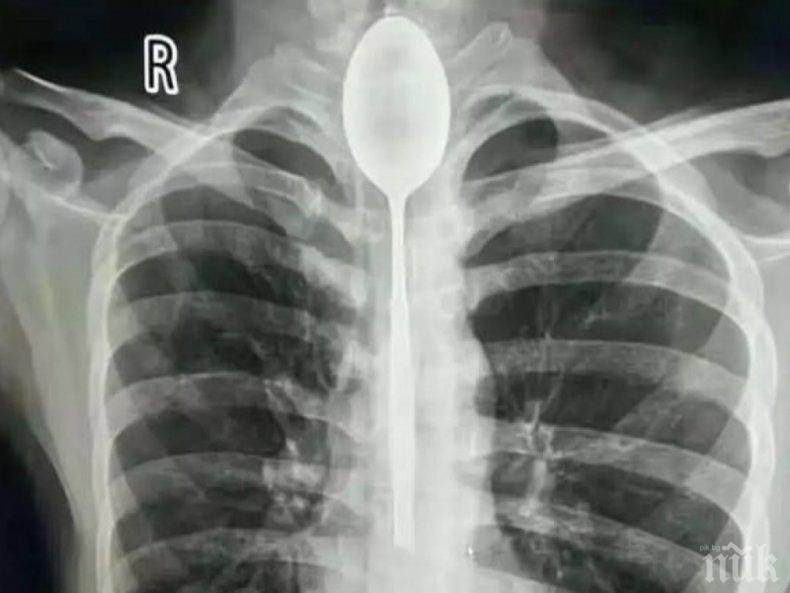

Китаец живял една година със заседнала супена лъжица в стомаха, която той глътнал при пиянски запой, пише в. "Дейли мейл".

Лекари с изненада се натъкнали на прибора, попаднал през хранопровода на 26-годишния пациент от провинция Синцзян. Младият мъж се опитал да направи трик пред компанията, след като бил употребил доста голямо количество алкохол.

Лъжицата се появила на рентгеновата снимка при прегледа на пациента. Китаецът потърсил медицинска помощ, защото постоянно се оплаквал от болки в корема и затруднено дишане, предава Дарик. Когато видял негатива, младият мъж не се изненадал и се сетил за трика отпреди една година. Той искал да удиви приятелите си по чашка, като глътне лъжицата, а след това я изтегли с връвчица. Но конецът се скъсал и лъжицата си останала в корема му. Тя не му пречела и затова той не се обърнал веднага за помощ към лекарите.

При последния преглед медиците решили да не пристъпват към пълна операция. Те успели да извадят кухненския прибор от устата на пациента докато той бил под упойка.